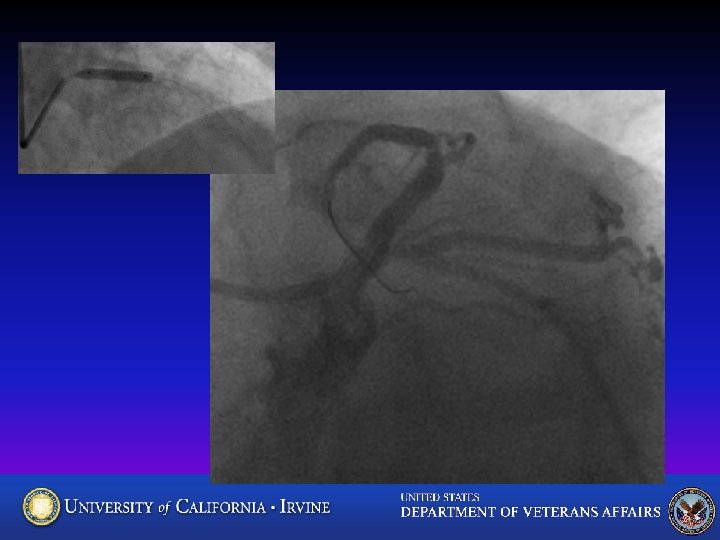

71 yo Man with typical angina, pos stress, CAD risk factors What’s your best approach?

FFR CFX=0. 88

LAD Xience 3. 5 x 18. 2 nd LAD lesion? All done? ? FFR = 0. 68